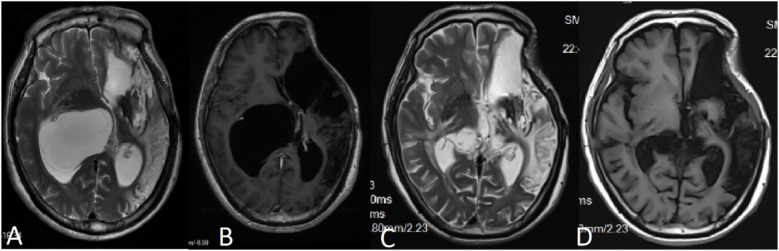

The simultaneous occurrence of intracranial aneurysms and intracranial arachnoid cysts is a rare clinical observation, with the majority of documented instances demonstrating ipsilateral presentation. In this report, we describe an atypical case involving the development of a secondary arachnoid cyst subsequent to the rupture of an intracranial aneurysm. Notably the cyst was situated contralaterally to the site of the aneurysm rupture and outside the surgical field. The patient's clinical history and imaging studies confirmedcorroborated the secondary nature of the cyst, which is postulated to have resulted from inflammatory responses triggered by a subarachnoid hemorrhage (SAH). The patient underwent neuroendoscopic partial resection of the cyst wall and lateral ventriculostomy, leading to a significant improvement in neurological dysfunction symptoms associated with the secondary arachnoid cyst. Follow-up cranial MRI demonstrated a substantial reduction in the cyst's volume, with no evidence of subsequent hydrocephalus or cyst enlargement. This case enhances the comprehension of the pathophysiological mechanisms underlying the formation of contralateral arachnoid cysts subsequent to aneurysm rupture and emphasizes the necessity of acknowledging arachnoid cysts as potential delayed complications associated with aneurysmal subarachnoid hemorrhage (aSAH).

颅内动脉瘤和颅内蛛网膜囊肿同时发生是一种罕见的临床观察,大多数记录的病例显示同侧表现。在这个报告中,我们描述了一个不典型的病例,涉及颅内动脉瘤破裂后继发性蛛网膜囊肿的发展。值得注意的是,囊肿位于动脉瘤破裂部位的对侧和手术野外。患者的临床病史和影像学检查证实了囊肿的继发性,推测是由蛛网膜下腔出血(SAH)引发的炎症反应引起的。患者接受了神经内窥镜部分切除囊肿壁和侧脑室造口术,继发性蛛网膜囊肿相关的神经功能障碍症状明显改善。后续颅脑MRI显示囊肿体积明显缩小,未见脑积水或囊肿增大。本病例加强了对动脉瘤破裂后对侧蛛网膜囊肿形成的病理生理机制的理解,并强调了将蛛网膜囊肿视为动脉瘤性蛛网膜下腔出血(aSAH)相关的潜在延迟并发症的必要性。